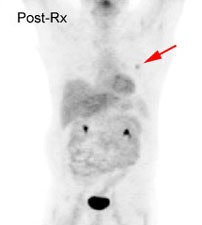

Response to treatment: 58 year old male with a left upper lobe non-small cell lung cancer and contralateral right hilar lymphadenopathy (blue arrow). FDG imaging also identified uptake in the inferolateral aspect of the right hemithorax which most likely represented a pleural metastasis with probable chest wall/rib invasion (black arrow). Because of the advanced stage of disease, the patient received radiation and chemotherapy. Follow-up PET FDG imaging demonstrated decreased tracer uptake and decreased size of the primary lesion in the left upper lobe (red arrow). The metastates in the right hilum, as well as the right pleura or chest wall have virtually resolved. Unfortunately, despite a positive response to treatment the presence of residual FDG activity in this patient would indicate a long term poor prognosis. Case courtesy of the North Texas Clinical PET Institute and CTI. |